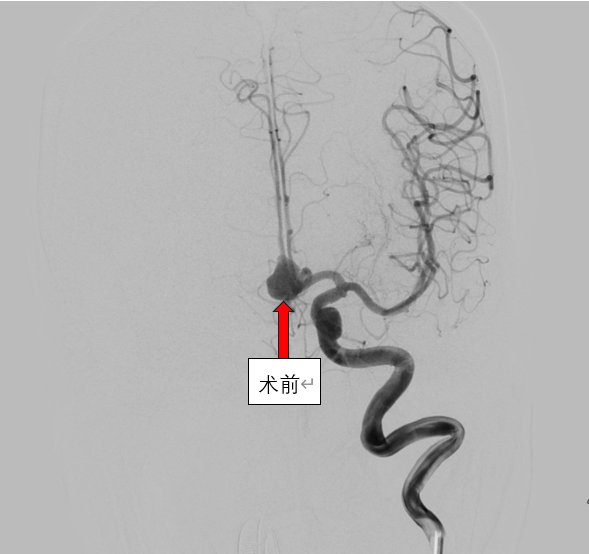

那个深夜,急诊科的警报划破宁静。一名患者因剧烈头痛、呕吐急诊入院,头颅CT提示典型的“急性蛛网膜下腔出血”——这往往是颅内血管破裂的凶险信号。时间就是大脑,时间就是生命!医院神经内科介入团队闻讯而动,绿色通道瞬间开启。急诊脑血管造影(DSA)结果揪紧了所有人的心:前交通动脉瘤破裂,血液正从薄弱处涌出,威胁着关键脑组织。

这是一场不容有失的“微雕”手术。在高精度数字减影血管造影的引导下,在介入导管室的密切配合下,介入团队犹如拥有“透视眼”,将微导管如丝般柔顺地导航至病灶处。随后,比发丝还细的铂金弹簧圈被精准、稳定地送入动脉瘤囊内,直到将那个致命的膨出部位完全填塞,血流不再涌入,破裂风险被彻底解除。手术台上,危机化解;监护室里,生命体征渐趋平稳。从命悬一线到转危为安,再到最终好转出院,这场与死神的极速竞赛,彰显了医院在急诊脑血管介入救治方面的强大实力与高效协作。